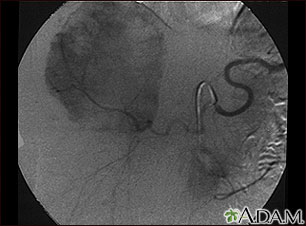

Your health care provider will do a physical exam to diagnose a hemangioma. If the buildup of blood vessels is deep inside the body, a CT or MRI scan may be needed.